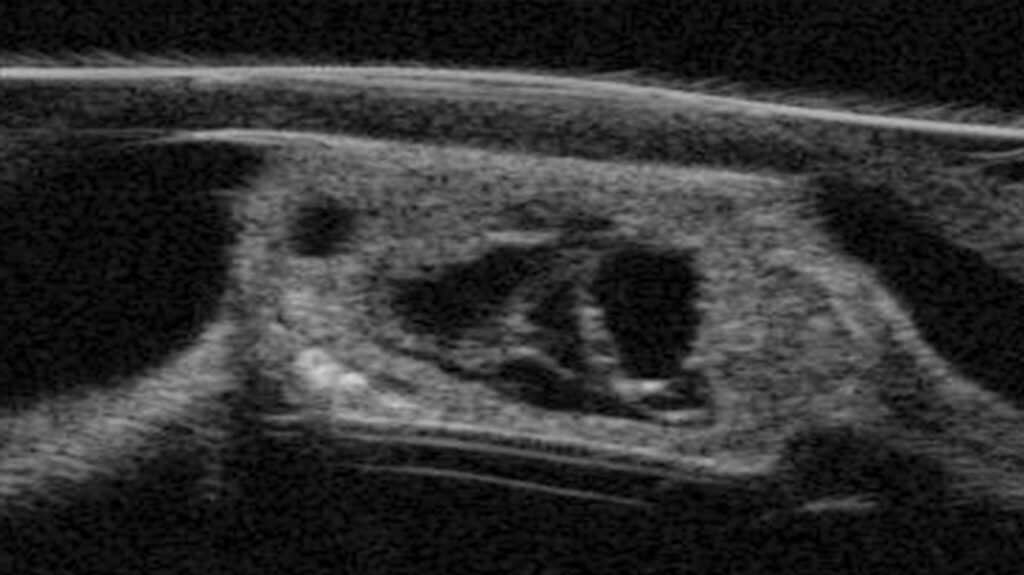

Update Jady (5)

Veröffentlicht am 7. September 2022Originalgröße 1366 × 767

Veröffentlicht inUpdate zu Jady